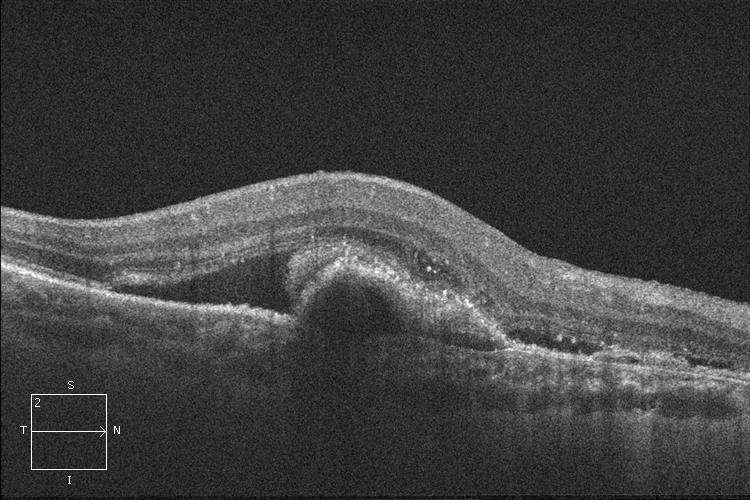

La Degeneración Macular Asociada a la Edad (DMAE) húmeda o exudativa se trata con inyecciones intravítreas de fármacos antiangiogénicos. Suelen ser necesarias varias inyecciones antes de lograr controlar el crecimiento de los vasos sanguíneos responsables de la enfermedad. Las inyecciones intravítreas pueden realizarse en una sala limpia o quirófano, con anestesia local y en condiciones de esterilidad.

OCT. DMAE húmeda o exudativa antes del tratamiento con inyecciones intravítreas.